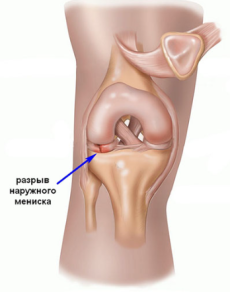

Разрывы корня мениска (РКМ) определяются как полный радиальный разрыв, локализующийся в пределах 1 см от места прикрепления к большеберцовой кости, либо как отрыв мягкотканых или костных фрагментов в области корня. В последние годы данной патологии уделяется всё больше внимания, поскольку результаты исследований свидетельствуют о неблагоприятных исходах лечения, сопоставимых с последствиями частичной менискэктомии [4, 5].

Разрывы корня латерального мениска чаще всего возникают вследствие острых травм, сопровождающихся значительной ударной нагрузкой, и нередко сочетаются с по- Journal of modern medicine №1 (12), Tome 2, 2026 1193 вреждением связочного аппарата. В отличие от них, разрывы корня медиального мениска чаще имеют дегенеративный характер и преимущественно встречаются у пациентов старшего возраста [6].

Медиальный и латеральный мениски — это серповидные фиброзно-хрящевые структуры, которые занимают от половины до двух третей площади тибиального плато. Их главная задача заключается в передаче нагрузки через тибиофеморальный сустав. Это снижает давление на окружающий суставной хрящ и способствует долговременному сохранению целостности сустава [6]. Менисковые корни играют ключевую роль, фиксируя мениски к передней и задней частям тибиального плато. Эти прикрепления выполняют важную биомеханическую функцию, преобразуя осевые нагрузки в кольцевые напряжения, предотвращая выпячивание мениска и поддерживая нормальную кинематику коленного сустава [4, 5].

Корни мениска. Анатомия корней мениска хорошо изучена. Каждое из четырех мест их прикрепления отличается по естественной прочности и площади контакта. Передний медиальный (ПМ), задний медиальный (ЗМ) и задний латеральный (ЗЛ) корни содержат центральные пучки волокон, а также дополнительные связывающие элементы.

Передний латеральный (ПЛ) корень переплетается с передней крестообразной связкой (ПКС), перекрывая её и проходя под точкой её прикрепления к большеберцовой кости. Этот корень однороден по всей длине, без дополнительных прикрепляющихся волокон. Суставной хрящ. Суставной хрящ состоит из коллагена II типа и обладает высокоорганизованной структурой [15]. Повреждение этого хряща при травме корня мениска — не редкость. При этом риск травмы выше при остром повреждении латерального корня по сравнению с дегенеративным разрывом медиального корня [6]. Бессосудистая природа суставного хряща ограничивает его способность к заживлению, и в настоящее время активно изучаются методы восстановления для устранения негативных последствий его повреждения. Кроме того, потеря кольцевых напряжений, вторичная к разрыву корня, создает сверхфизиологические нагрузки на хрящ колена. Эти факторы повышают риск развития ОА и необходимости тотального эндопротезирования коленного сустава (ТЭКС) [9, 15].